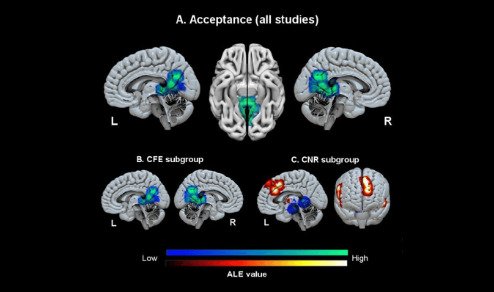

Este año, los científicos han descubierto que al ‘alternar’ las frecuencias en un patrón fractal, se consigue emular el ciclo de la naturaleza al crear nuevas conexiones neuronales, estimulando con éxito la corteza prefrontal.

Mediante una fusión de los efectos de sincronización hemisferial y neuronal.

Sincronización Hemisferial + Neuronal = Activación Prefrontal

Resultado: Capacidad de Cognición Optimizada

▪️▫️▫️ Capa 1 de 3:

Tecnología Interaural de Sincronización Hemisferial

Conecta Ambos Hemisferios

La primera capa de la tecnología HybridWave™ potencia este fenómeno.

Gracias a su tecnología de diferencia interaural, se logra sincronización hemisferial.

Sincronizando tus ondas cerebrales entre hemisferios para liberar tu máximo potencial cognitivo.

Como Da Vinci, puedes activar la intuición del hemisferio derecho y la lógica del izquierdo en perfecta armonía, accediendo a una inteligencia más profunda y multidimensional.

▪️▪️▫️ Capa 2 de 3:

Tecnología Isocrónica de Activación Neuronal

Activa tu Potencial Neuronal

La segunda capa de la frecuencia híbrida, impulsada por HybridWave™.

Utiliza pulsos isocrónicos para inducir un estado de sincronización neuronal profunda.

Afinando el ritmo y la vibración de la actividad eléctrica de tu cerebro por medio de la frecuencia.

Esto optimiza tu enfoque, y desbloquea un estado de alto rendimiento mental.

▪️▪️▪️ Capa 3 de 3:

Tecnología Fractal de Activación Prefrontal

Despierta tu Súpercerebro

HybridWave™ amplifica la activación del Neocórtex.

Gracias a su tercera capa de tecnología-fractal de activación prefrontal.

Amplifica la neuroplasticidad, mejorando la capacidad de aprender y adaptarse en tiempo real.

Al fusionar los efectos de sincronización hemisferial y neuronal, con la activación prefrontal,

accedes a un nivel de pensamiento reservado para los genios.

Sincronización Hemisferial + Activación Prefrontal + Sincronización Neuronal = Capacidad de Cognición Optimizada